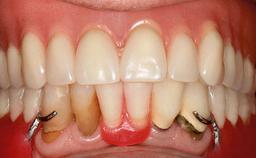

Mandibular Overdenture Supported by a CAD/CAM-milled Bar with Long Distal Extensions on Two Conventionally Loaded Implants

Defining Characteristics Fully edentulous lower jaw to be rehabilitated with an implant-borne removable overdenture

Loading Protocol Conventional/early

Occlusal Scheme/Issues Balanced